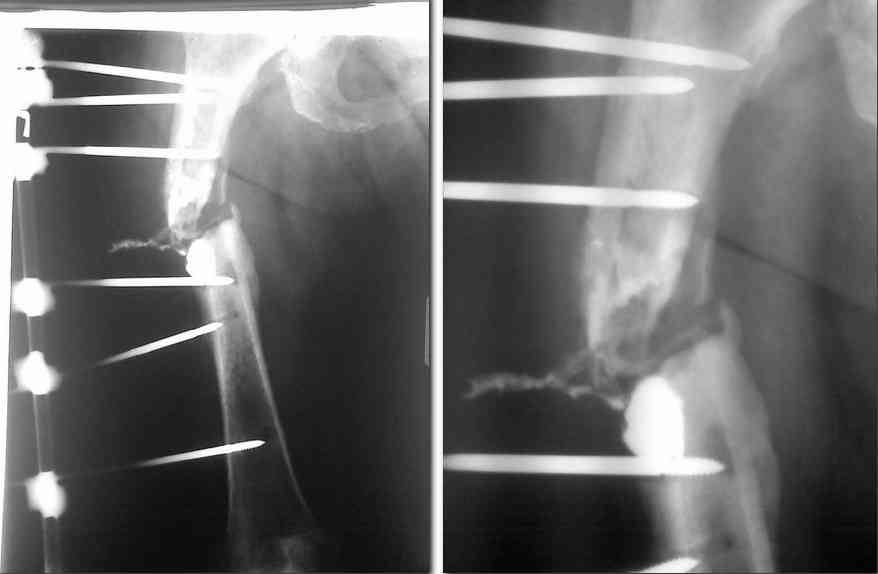

В момент поступления: укорочение бедра 4-5 см, в области послеоперационного рубца 2 свищевых отверстия 1-1.5 см в диаметре, по передней поверхности бедра свищ 1.5см в диаметре, выделяется густой гнойный ексудат. Вокруг стержней воспалительная реакция, серозно-гнойная ексудация. Патологическая подвижность. Посев-роста нет. Фистулограма в приложении. Аппарат демонтирован, скелетное вытяжение. Раны в местах стержней зажили.

Вчера прооперирована: фистулонекректомия, экономная резекция концов фрагментов, фиксация с укорочением и компрессией в спице-стержневом АВН (5 стержней в проксимальном фрагменет по передней и внешней поверхности и 2 кольца на 4 спицах в дистальном фрагменте) промывная система. Бусы с антибиотиком в данный момент больная не может себе позволить по финансовым причинам.